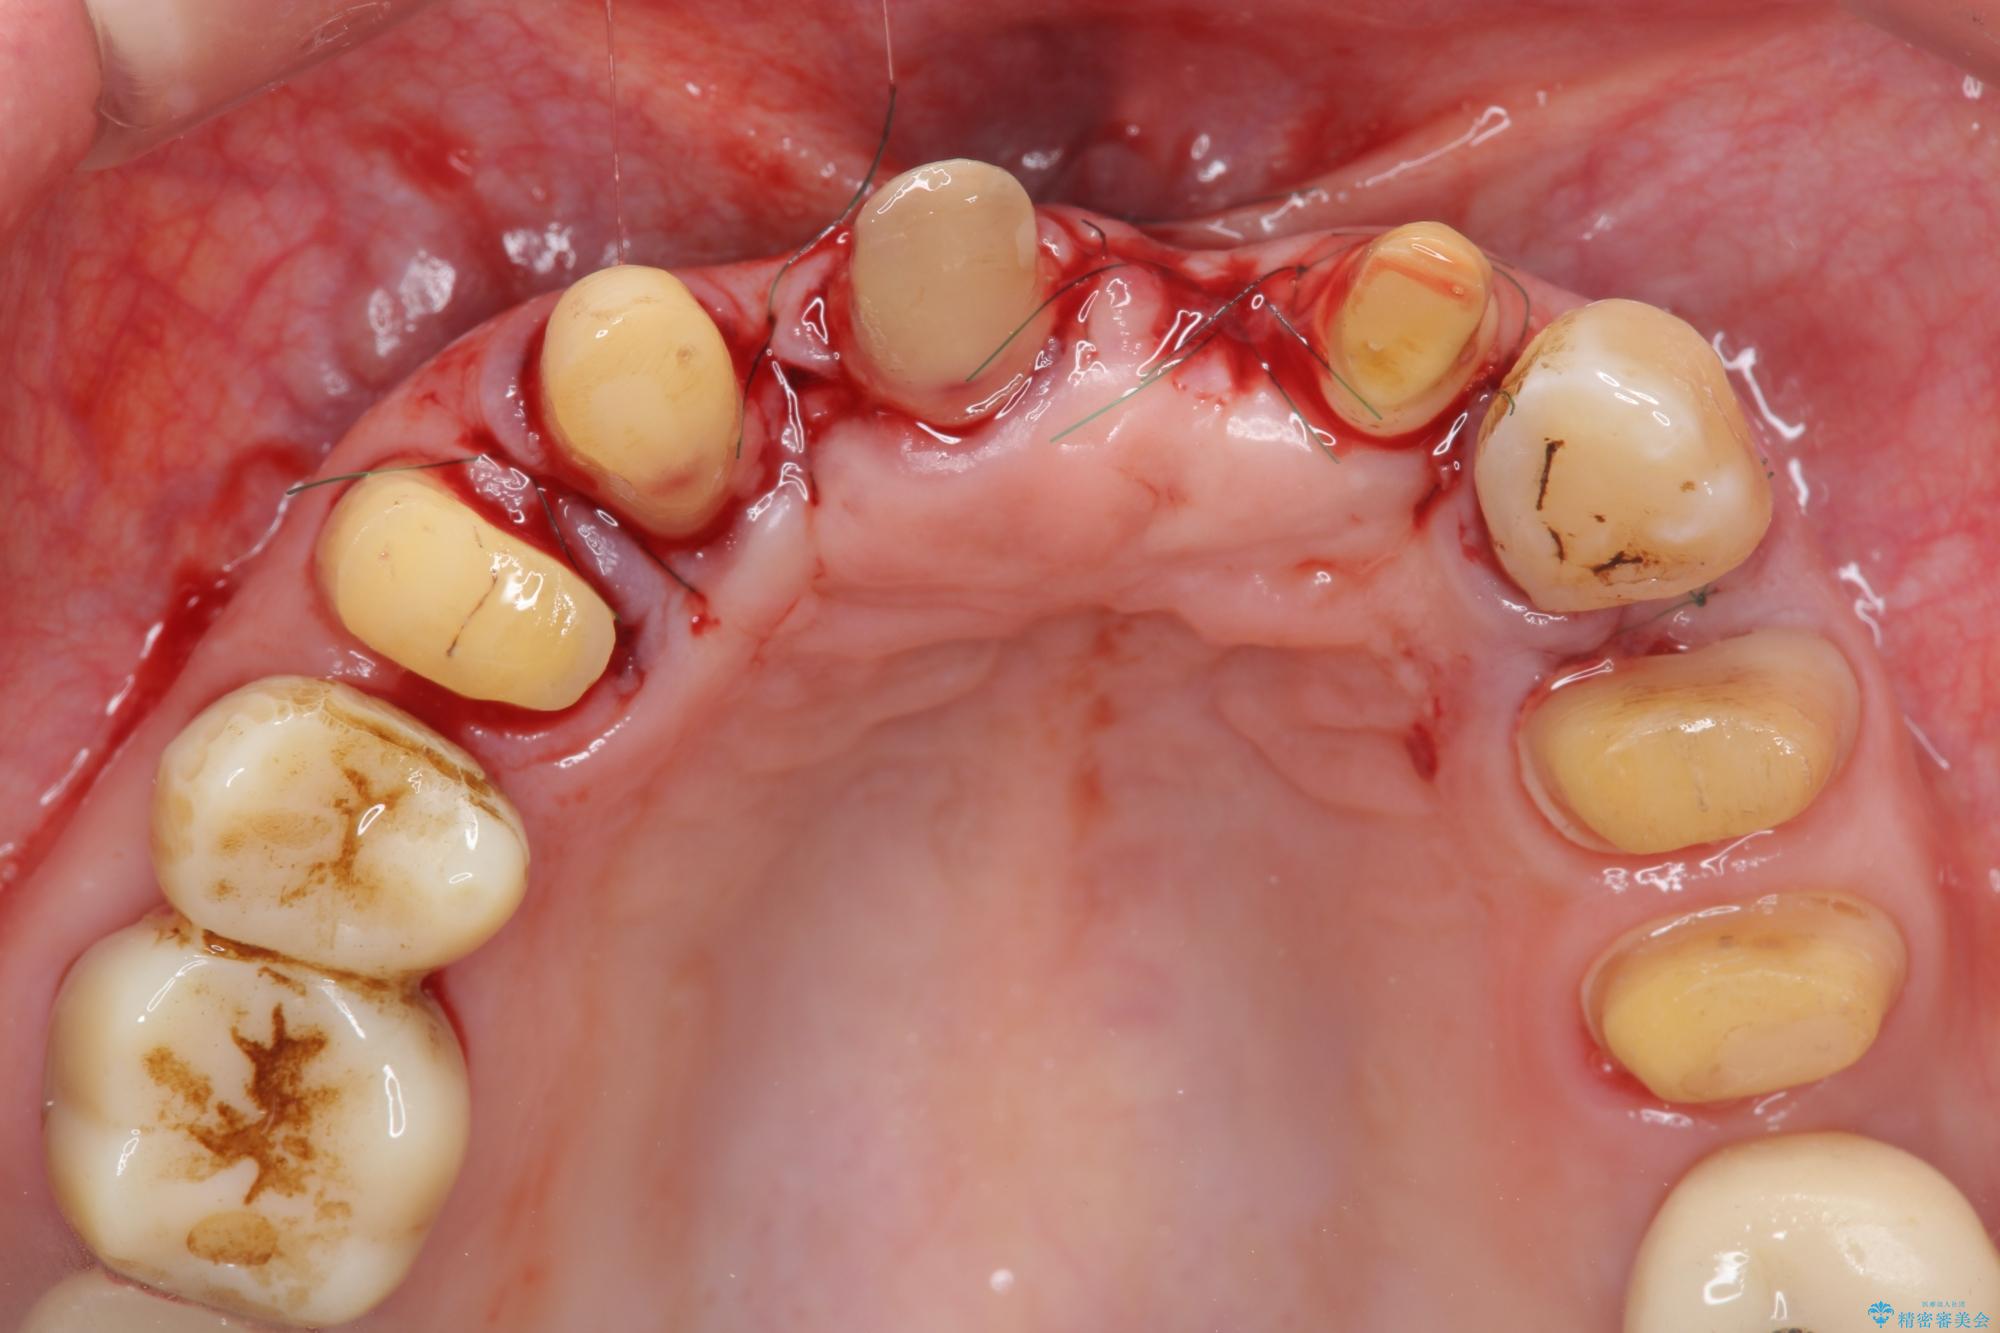

まず、保存の難しい歯を抜去したのち矯正治療を行い歯並びの改善、歯周ポケットを除去したことで安定した歯周環境、咬合関係を作り出すことができました。

矯正治療を事前に行ったことで全ての歯の神経を温存しセラミックブリッジを装着することができました。

治療中

歯の総合的なマネージメントを行う包括的歯科治療の実践[ 歯周病・矯正・セラミック補綴 ] 治療中画像 歯の総合的なマネージメントを行う包括的歯科治療の実践[ 歯周病・矯正・セラミック補綴 ] 治療中画像 歯の総合的なマネージメントを行う包括的歯科治療の実践[ 歯周病・矯正・セラミック補綴 ] 治療中画像 歯の総合的なマネージメントを行う包括的歯科治療の実践[ 歯周病・矯正・セラミック補綴 ] 治療中画像 歯の総合的なマネージメントを行う包括的歯科治療の実践[ 歯周病・矯正・セラミック補綴 ] 治療中画像 歯の総合的なマネージメントを行う包括的歯科治療の実践[ 歯周病・矯正・セラミック補綴 ] 治療中画像 歯の総合的なマネージメントを行う包括的歯科治療の実践[ 歯周病・矯正・セラミック補綴 ] 治療中画像 歯の総合的なマネージメントを行う包括的歯科治療の実践[ 歯周病・矯正・セラミック補綴 ] 治療中画像 歯の総合的なマネージメントを行う包括的歯科治療の実践[ 歯周病・矯正・セラミック補綴 ] 治療中画像 歯の総合的なマネージメントを行う包括的歯科治療の実践[ 歯周病・矯正・セラミック補綴 ] 治療中画像 歯の総合的なマネージメントを行う包括的歯科治療の実践[ 歯周病・矯正・セラミック補綴 ] 治療中画像